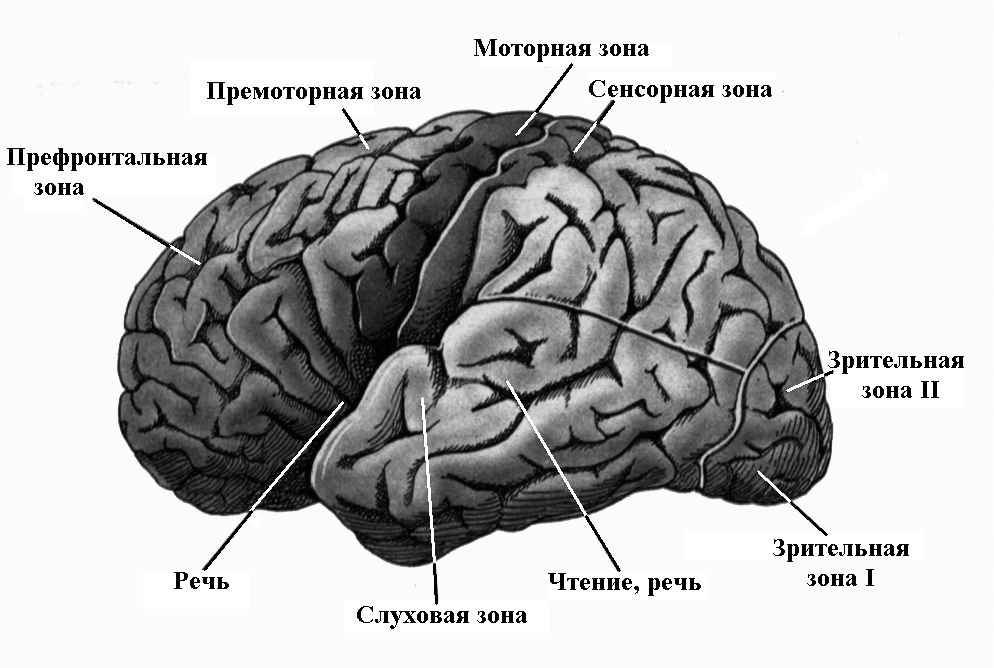

Схема чувствительных зон новой коры мозга